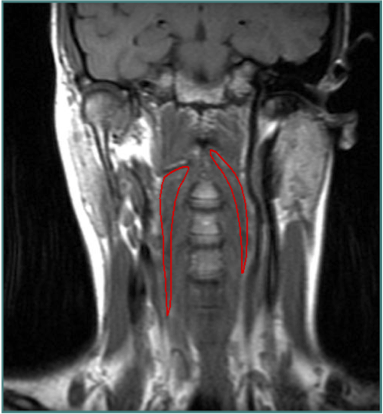

LATEROCOLLIS

Larynx shifted relative to sternum

LATERAL SHIFT

Secondary to lateral flexion of the spine and flexion of the head in the opposite direction.

Line from Sternum to larynx